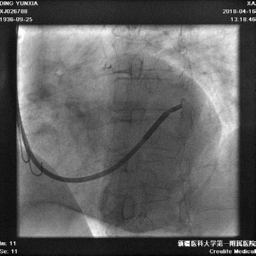

电极植入

● 导丝先行,鞘中鞘作支撑缓慢进入电极。

● 反复尝试电极第四个位点始终无法进入,最终保证前三位点参数,测试左室电极良好。

● 植入心房电极和右室除颤电极,连接起搏器。

冠状静脉造影

● 十极标测电极进入窦口后总是超选小分支,进入过程中逆向旋转十极标测电极,顺利避开小分支开口,进入主干,造影显示可用后静脉和侧静脉各一个

鞘中鞘超选靶血管

● 使用鞘中鞘超选入靶血管造影,明确靶血管远端情况。

植入左室电极

● 首选后静脉,通过鞘中鞘递送左室电极,深插鞘中鞘作支撑,电极始终无法送达远端,考虑患者血管狭窄导致,更换靶血管,从侧静脉递送电极至远端。